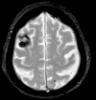

Varón de 54 años con antecedentes de linfoma primario del sistema nervioso central de células grandes diagnosticado en 2010 por alteración conductual y deterioro cognitivo rápidamente progresivo. Recibió quimioterapia (carmustina, metotrexato y Ara-C: esquema BAM,...

Neurología: NeurooncologíaEtiología: NeoplasiasDiagnóstico final: Recidiva de linfoma cerebral primarioNivel de certeza: